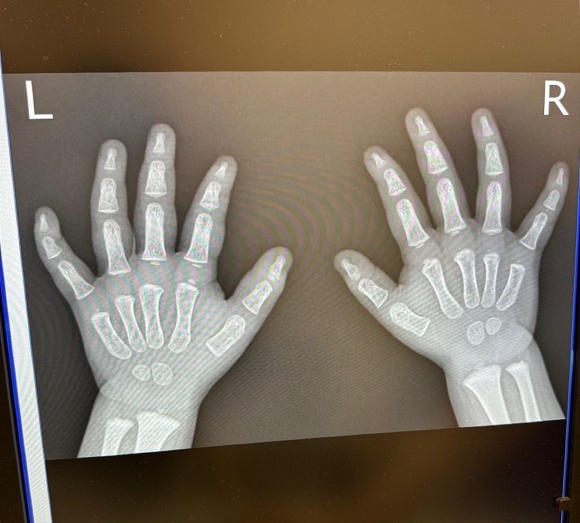

かわいいレントゲン写真を投稿したのは、Xユーザーの「ココ3」(@shonancoco3)さん。お子さんが手を痛めてしまったのでレントゲンを撮影したところ、大人とは全く違う小さな骨格と、ぷにぷにしていそうな小さな手が写し出されたのでした。これにはお父さんも医師もかわいさににっこりしちゃいますね。

この投稿には、「めっちゃかわいい!」「こんなストレートにかわいい骨格あるのね」「えっ!? デフォルメされてる訳じゃないんですよね?」「かわいい生き物は骨までかわいい」「なぜかクスってなりますね」といったコメントが寄せられています。